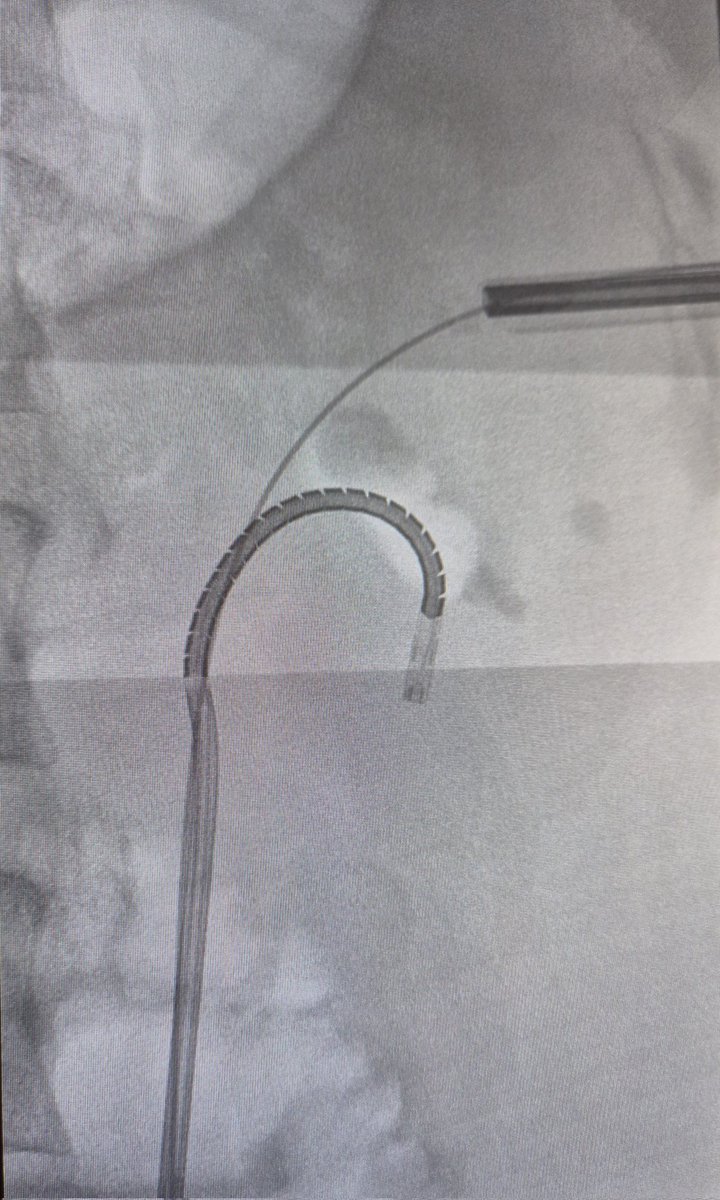

Advanced supine #PCNL workshop at #HURH with @CoralManso hosting colleagues from Spain & Portugal US & fluoroscopy Complex cases #uppercalyx

#SBES

#miniECIRS Thanks to @bsc_urology for the support #lithovueElite Proud of my team!

Grandes consejos para el acceso a cáliz superior!

🎯 Proud of sharing our experience in the access to the upper calyx in supine position 📄 Published in Urolithiasis https://t.co/9NVHpYJ9V0 👀 Have a look at our technique & 📊 results in the first 100 cases Thanks to my team for the effort! #PCNL

#uppercalyx

#teamwork